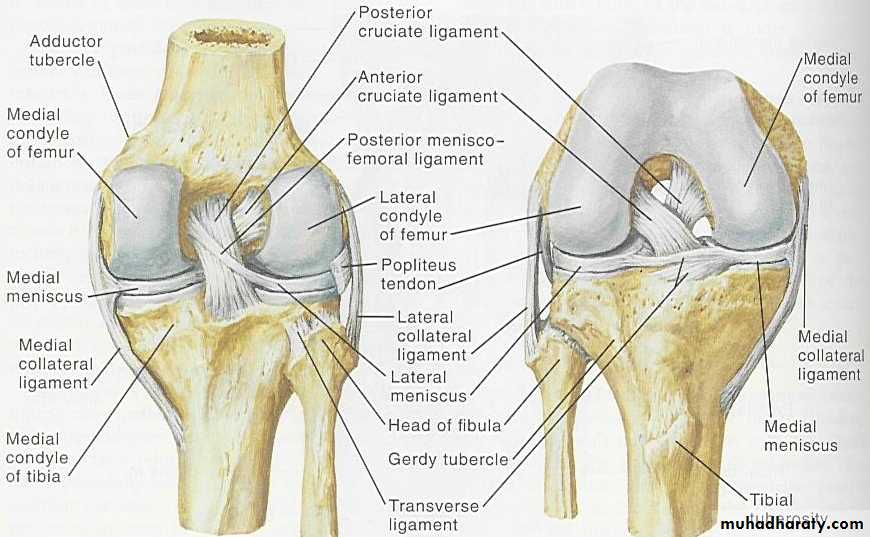

Anatomy of knee joint

Meniscal tearsThe menisci have arole in(1)increase the stability of the knee,(2)controlling the complex rolling and gliding actions of the joint and(3)distribution load during movement.

Medial meniscus is affected more than lateral because its attachments to the capsule make it less mobile.